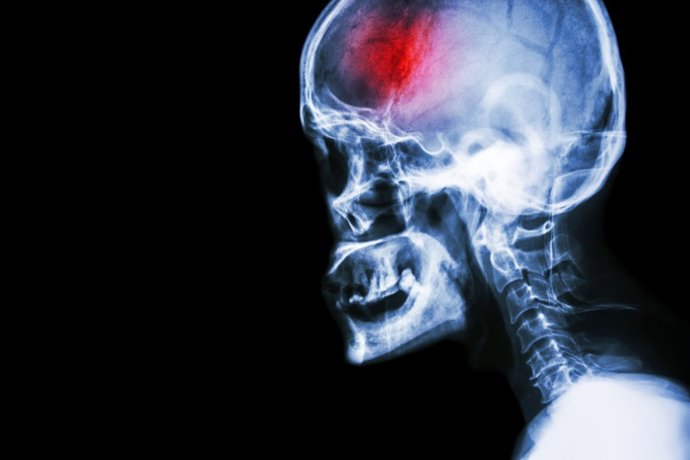

Neuropediatras alertan de que el ictus es una de las principales causas de mortalidad infantil

Archivo - Ictus.

Archivo - Ictus. - GETTY IMAGES/ISTOCKPHOTO / STOCKDEVIL - Archivo